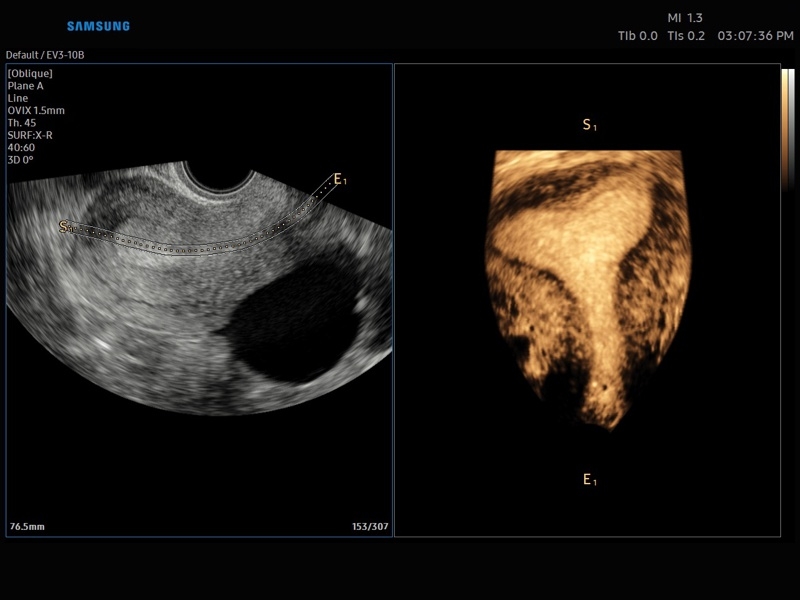

• Акушерство и гинекология

• OVIX(Oblique View eXtended) - получение фрагмента трехмерного изображения (в виде нескольких полупрозрачных сканов, последовательно наложенных один на другой) в направлении произвольного косого среза трехмерного объекта исследования.

• Модуль Realistic Vue - программа реконструкции реалистичного 3D УЗИ, при котором на объемное изображение накладывается виртуальный источник освещения. Специальный процессинговый алгоритм воспроизводит трехмерную анатомию плода с исключительной детализацией.

• МодульCrystal Vue- программа реконструкции прозрачного 3D УЗИ, которое получается при одновременном усилении внутренних и наружных структур. Применяется для визуальной оценки состояния плода и матки, помогает лучше идентифицировать мягкие ткани и кости.